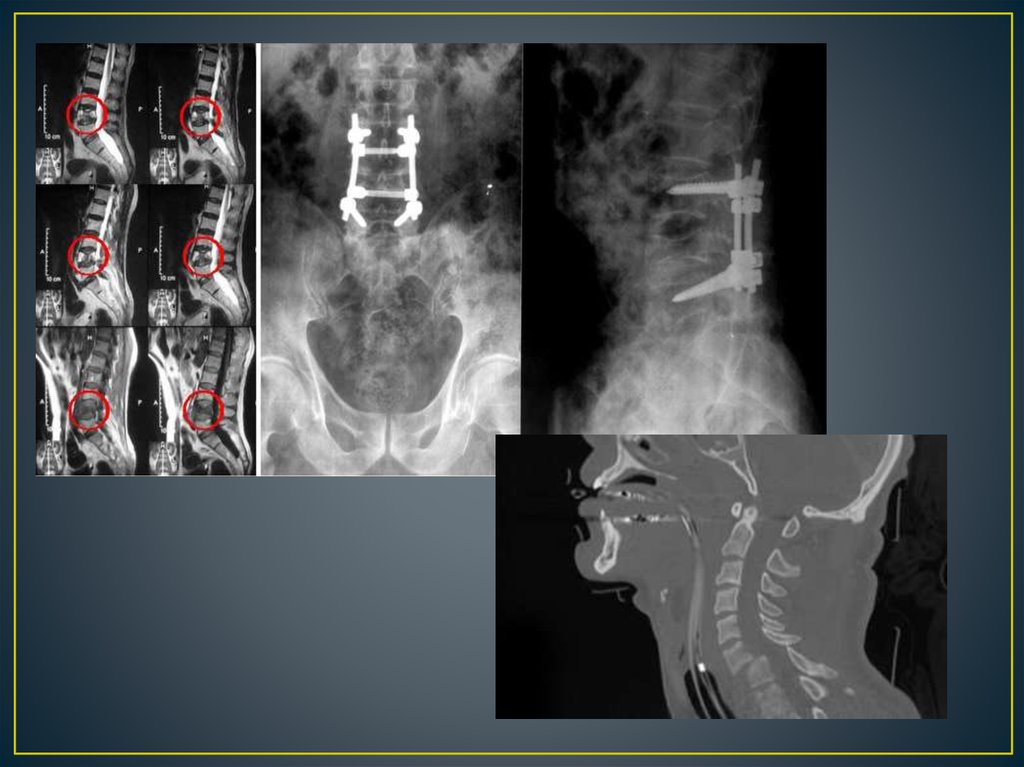

Позвоночно – спинальная травма